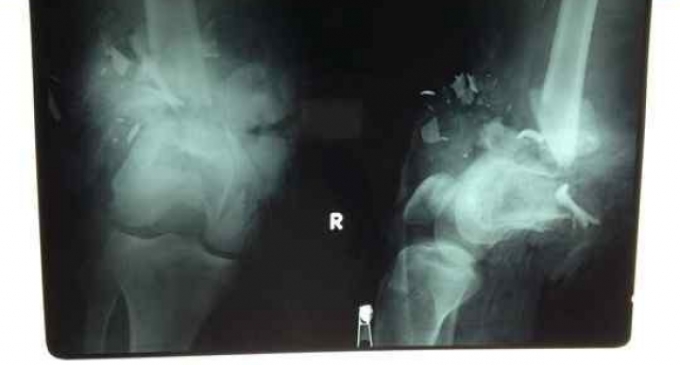

Trước đó, anh Th. nhập viện cấp cứu trong tình trạng đùi gần đứt lìa, chỉ còn dính lại một vạt da, dập nát cơ và xương. Các bác sĩ đã xử trí cấp cứu, cắt lọc bỏ các cơ hoại tử, bỏ xương đã bị dập nát…, sau đó tiến hành nối lại các mạch máu, dây thần kinh và dây chằng, đồng thời ghép lại da cứu chân bệnh nhân. Đến ngày 2-4, các dấu hiệu cho thấy chân phải của Th. được cứu sống.

Các bác sĩ chạy đua thời gian nối ráp hàng lọat bộ phận cơ, gân, dây thần kinh... để cứu chân cho anh Th.